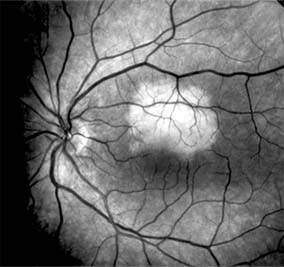

Chapter 10: Retina DISEASES OF THE MACULA AGE-RELATED MACULAR DEGENERATION Age-related macular degeneration is the leading cause of permanent blindness in the elderly. The exact cause is unknown, but the incidence increases with each decade over age 50. Other associations besides age include race (usually Caucasian), sex (slight female predominance), family history, and a history of cigarette smoking. The disease includes a broad spectrum of clinical and pathologic findings that can be classified into two groups: nonexudative ("dry") and exudative ("wet"). Although both types are progressive and usually bilateral, they differ in their manifestations, prognosis, and management. The more severe exudative form accounts for approximately 90% of all cases of legal blindness due to age-related macular degeneration. 1. NONEXUDATIVE MACULAR DEGENERATION Nonexudative age-related macular degeneration is characterized by variable degrees of atrophy and degeneration of the outer retina, retinal pigment epithelium, Bruch's membrane and choriocapillaris. Of the ophthalmoscopically visible changes in the retinal pigment epithelium and Bruch's membrane, drusen are the most typical (Figure 10-1). Drusen are discrete, round, yellow-white deposits of variable size beneath the pigment epithelium and are scattered throughout the macula and posterior pole. With time, they may enlarge, coalesce, calcify, and increase in number. Histopathologically, most drusen consist of focal collections of eosinophilic material lying between the pigment epithelium and Bruch's membrane; they therefore represent focal detachment of the pigment epithelium. In addition to drusen, clumps of pigment irregularly dispersed within depigmented areas of atrophy may progressively appear throughout the macula. The level of associated visual impairment is variable and may be minimal. Fluorescein angiography demonstrates irregular patterns of retinal pigment epithelial hyperplasia and atrophy. Electrophysiologic testing in most patients is normal. There is no generally accepted treatment or means of prevention of this type of macular degeneration. Laser retinal photocoagulation appears to have a beneficial effect on drusen but has not yet been shown to improve visual outcome. Although high plasma levels of antioxidants are associated with a reduced risk of age-related macular degeneration, the use of vitamin supplements does not appear to be preventive. Most patients with macular drusen never experience significant loss of central vision; the atrophic changes may stabilize or progress slowly. However, the exudative stage may develop suddenly at any time, and in addition to regular ophthalmic examinations, patients are given an Amsler grid ( 2. EXUDATIVE MACULAR DEGENERATION Although patients with age-related macular degeneration usually manifest nonexudative changes only, the majority of patients who experience severe vision loss from this disease do so from the development of subretinal neovascularization and related exudative maculopathy. Serous fluid from the underlying choroid can leak through small defects in Bruch's membrane, causing focal detachment of the pigment epithelium. Additional fluid may lead to further separation of the overlying sensory retina, and vision usually decreases if the fovea is involved. Retinal pigment epithelial detachments may spontaneously flatten, with variable visual results, and leave a geographic area of depigmentation at the involved site. Ingrowth of new vessels from the choroid into the subretinal space is the most important change that predisposes patients with drusen to macular detachment and irreversible loss of central vision. These new vessels grow in a flat cartwheel or sea-fan configuration away from their site of entry into the subretinal space. The clinical changes of early subretinal neovascularization are subtle and may be easily overlooked; during this occult stage of new vessel formation, the patient is asymptomatic, and the new vessels may not be apparent either ophthalmoscopically or angiographically. The ophthalmologist must maintain a high index of suspicion that subretinal neovascularization is present whenever a patient with evidence of age-related macular degeneration has sudden or recent central vision loss, including blurred vision, distortion, or a new scotoma. If the fundus examination reveals subretinal blood, exudate, or a grayish-green choroidal lesion in the macula, there is great likelihood that neovascularization is present, and a fluorescein or indocyanine green angiogram should be obtained promptly to determine if a treatable lesion can be identified. Although some subretinal neovascular membranes may spontaneously regress, the natural course of subretinal neovascularization in age-related macular degeneration is toward irreversible loss of central vision over a variable period of time. The sensory retina may be damaged by long-standing edema, detachment, or underlying hemorrhage. Furthermore, a hemorrhagic detachment of the retina may undergo fibrous metaplasia, resulting in an elevated subretinal mass called a disciform scar. This elevated fibrovascular mound of variable size represents the cicatricial end stage of exudative age-related macular degeneration. It is usually centrally located and results in permanent loss of central vision. Treatment In the absence of subretinal neovascularization, no medical or surgical treatment of serous retinal pigment epithelial detachment is of proved benefit. The use of parenteral alpha interferon, for example, has not been effective for this disease. However, if a well-defined extrafoveal ( Krypton laser photocoagulation of juxtafoveal (<200 Following successful photocoagulation of a subretinal neovascular membrane, recurrent neovascularization either contiguous with or remote from the laser scar may occur in one-half of cases by 2 years. Recurrence is often accompanied by severe vision loss, so that careful monitoring with Amsler grids, ophthalmoscopy, and angiography is essential. Low-dose radiotherapy has provided encouraging results in patients with subfoveal neovascularization. Patients with impaired central vision in both eyes may benefit from a variety of low vision aids. CENTRAL SEROUS CHORIORETINOPATHY Central serous chorioretinopathy is characterized by serous detachment of the sensory retina as a consequence of focal leakage of fluid from the choriocapillaris through a defect in the retinal pigment epithelium (Figures 10-2 and 10-3). This disease typically affects young to middle-aged men and may be related to life stress events. Most patients present with the sudden onset of blurred vision, micropsia, metamorphopsia, and central scotoma. Visual acuity is often only moderately decreased and may be improved to near-normal with a small hyperopic correction. The diagnosis is made by slitlamp examination of the fundus; the presence of serous detachment of the sensory retina in the absence of ocular inflammation, subretinal neovascularization, an optic pit, or a choroidal tumor is diagnostic. The retinal pigment epithelial lesion appears as a small, round or oval, yellowish-gray spot that is variable in size and may be difficult to detect without the aid of fluorescein angiography. Fluorescein dye leaking from the choriocapillaris may accumulate below the pigment epithelium or sensory retina, resulting in a variety of patterns including the well-recognized smokestack configuration. Approximately 80% of eyes with central serous chorioretinopathy undergo spontaneous resorption of subretinal fluid and recovery of normal visual acuity within 6 months after the onset of symptoms. Despite normal acuity, however, many patients have a mild permanent visual defect, such as a decrease in color sensitivity, micropsia, or relative scotoma. Twenty to 30 percent of patients will have one or more recurrences of the disease, and complications-including subretinal neovascularization and chronic cystoid macular edema-have been described in patients with frequent and prolonged serous detachments. The cause of central serous chorioretinopathy is unknown; there is no convincing evidence that the disease is either infectious or due to retinal pigment epithelial dystrophy. Argon laser photocoagulation directed to the active leak significantly shortens the duration of the sensory detachment and hastens the recovery of central vision, but there is no evidence that prompt photocoagulation reduces the chance of permanent loss of visual function. Although the complications of retinal laser photocoagulation are few, it is probably not advisable to recommend immediate photocoagulation treatment in all patients with central serous chorioretinopathy. The duration and location of disease, the condition of the fellow eye, and occupational visual requirements are all considerations upon which treatment decisions are based. MACULAR EDEMA Retinal edema involving the macula may be associated with a variety of intraocular inflammatory diseases, retinal vascular diseases, intraocular surgery, inherited or acquired retinal degenerations, medications, macular membranes, or unknown causes. Macular edema may be diffuse, with nonlocalized intraretinal fluid causing thickening of the macula. When edema fluid accumulates in honeycomb-like spaces of the outer plexiform and inner nuclear layers, it is called cystoid macular edema. On fluorescein angiography, fluorescein dye leaks from the perifoveal retinal capillaries and accumulates in a flower-petal pattern about the fovea (Figure 10-4). The most widely recognized association with cystoid macular edema is intraocular surgery. Approximately 50% of eyes undergoing uneventful intracapsular cataract extraction and 20% of eyes undergoing extracapsular cataract extraction develop angiographic cystoid macular edema. Clinically significant edema usually occurs within 4-12 weeks postoperatively, but in some instances its onset may be delayed for months or years. Many patients with cystoid macular edema of less than 6 months' duration have self-limited leakage that will resolve without treatment. Topical or local (or both) anti-inflammatory therapy may be of value in restoring visual acuity in some patients with chronic postoperative macular edema. YAG laser vitreolysis (see Chapter 24) and surgical vitrectomy may be of benefit when the macular edema is associated with vitreous tissue incarcerated in the cataract wound or adherent to anterior segment structures. When an intraocular lens implant is the cause of postoperative macular edema due to its design, positioning, or inadequate fixation, removal of the lens implant can be considered. INFLAMMATORY DISORDERS INVOLVING THE MACULA Presumed Ocular Histoplasmosis Syndrome (Figures 10-5, 10-6 and 10-7) In this disease, serous and hemorrhagic detachments of the macula are associated with multiple peripheral atrophic chorioretinal scars and peripapillary chorioretinal scarring (see Chapter 7). The syndrome usually occurs in healthy patients between the third and sixth decades of life, and the scars are probably caused by an antecedent subclinical systemic infection with Histoplasma capsulatum. The macular detachments are due to subretinal neovascularization, and the visual prognosis depends on the proximity of the neovascular membrane to the center of the fovea. If the membrane extends inside the foveal avascular zone, only 15% of eyes will retain 20/40 vision. A macular scar may change over time, and 10% of patients with normal maculae will develop new atrophic scars in this region. The relative risk of developing macular subretinal neovascularization in the second eye of an affected patient is significant, and these patients should be instructed in the frequent use of the Amsler grid and the importance of prompt examination when changes are detected. Argon laser photocoagulation of a subretinal neovascular membrane outside the foveal avascular zone in symptomatic patients is of value in preventing severe vision loss. The surgical removal of submacular membranes may prove useful in preserving vision. Acute Multifocal Posterior Placoid Pigment Epitheliopathy (AMPPPE) AMPPPE typically affects healthy young patients who develop rapidly progressive bilateral vision loss in association with ophthalmoscopically visible multifocal flat gray-white subretinal lesions involving the pigment epithelium (Figure 10-8). The cause of this disease, which in many instances is associated with evidence of an influenza-like illness, is unknown; the course and nature of the illness suggests the possibility of viral infection. The characteristic feature of the disease is the rapid resolution of the fundus lesions and a delayed return of visual acuity to near-normal levels. Although the prognosis for visual recovery in this acute self-limited disease is good, many patients will identify small residual paracentral scotomas when carefully tested. Extensive pigmentary changes remaining during the late stages of AMPPPE may mimic widespread retinal degeneration; the clinical history and normal electrophysiologic findings aid in this differential diagnosis. Geographic Helicoid Peripapillary Choroidopathy This is a chronic progressive and recurrent multifocal inflammatory disease of the retinal pigment epithelium, choriocapillaris, and choroid. It characteristically involves the juxtapapillary retina and extends radially to involve the macula and peripheral retina. The active stage manifests itself as sharply demarcated gray-yellow lesions with irregular borders that appear to involve the pigment epithelium and choriocapillaris. Vitritis, anterior uveitis, and subretinal neovascularization have been associated with this disorder. Involvement is usually bilateral, and the cause is unknown. The natural history of this indolent inflammatory disease is variable and may correlate with the presence of disease in the fellow eye. Local or systemic corticosteroid treatment may be of benefit when active inflammation is present; laser photocoagulation is administered as indicated for the complication of subretinal neovascularization. Vitiliginous Chorioretinitis (Birdshot Retinochoroidopathy) This is a syndrome characterized by diffuse cream-colored patches at the level of the pigment epithelium and choroid, retinal vasculitis associated with cystoid macular edema, and vitritis. The associations with HLA-A29 and with retinal S-antigen suggest that this disease has a genetic predisposition and that retinal autoimmunity plays a role in its manifestations. In many cases, electroretinography, electro-oculography, and dark adaptation studies are abnormal. The course of the disease is that of exacerbation and remission with variable visual outcomes; visual loss has been attributed to chronic cystoid macular edema, optic atrophy, macular scarring, or subretinal neovascularization. Corticosteroid therapy has not proved effective against this disease. Acute Macular Neuroretinopathy Acute macular neuroretinopathy is characterized by the acute onset of paracentral scotomas and mild visual acuity loss accompanied by wedge-shaped parafoveal retinal lesions in the deep sensory retina of one or both eyes. The macular lesions are subtle, reddish-brown, and best seen with a red-free light. The patients are usually young adults with a history of acute viral illness. While the retinal lesions may fade, the scotomas tend to persist and remain symptomatic. Multiple Evanescent White Dot Syndrome This is an acute and self-limited unilateral disease that affects mainly young women and is characterized clinically by multiple white dots at the level of the pigment epithelium, vitreal cells, and transient electroretinographic abnormalities. The cause is unknown. There is no evidence of associated systemic disease. The retinal lesions gradually regress in a matter of weeks, leaving only minor retinal pigment epithelial defects. ANGIOID STREAKS Angioid streaks appear as irregular, jagged tapering lines that radiate from the peripapillary retina into the macula and peripheral fundus (Figure 10-9). The streaks represent linear crack-like dehiscences in Bruch's membrane. The lesions are rarely noted in children and probably develop in the second or third decade of life. Early in the disease the streaks are sharply outlined and red-orange or brown. Subsequent fibrovascular tissue growth may partially or totally obscure the streak margins. Nearly 50% of patients with angioid streaks have an associated systemic disease. Pseudoxanthoma elasticum, Paget's disease of bone, Ehlers-Danlos syndrome, and several hemoglobinopathies and hemolytic disorders have been associated with this retinal disease, but the most common association is with age-related degeneration of Bruch's membrane. Patients with angioid streaks should be warned of the potential risk of choroidal rupture from even relatively mild eye trauma. Older patients with the disease are at risk of developing serous and hemorrhagic detachments of the retina as a consequence of subretinal neovascularization. Laser treatment may be used to photocoagulate extrafoveal neovascular membranes; however, other neovascular membranes are likely to occur. Prophylactic treatment of angioid streaks before subretinal neovascularization develops is not recommended. MYOPIC MACULAR DEGENERATION Pathologic myopia is one of the leading causes of blindness in the United States and is characterized by progressive elongation of the eye with subsequent thinning and atrophy of the choroid and pigment epithelium in the macula. Peripapillary chorioretinal atrophy and linear breaks in Bruch's membrane ("lacquer cracks") are characteristic findings on ophthalmoscopy (Figure 10-10). The degenerative changes of the macular pigment epithelium resemble those found in the older patient with age-related macular degeneration. A characteristic lesion of this disease is a raised, circular, pigmented macular lesion called a Fuchs spot. Most patients are in the fifth decade when the degenerative macular changes cause a slowly progressive loss of vision; rapid loss of visual acuity is usually caused by serous and hemorrhagic macular degeneration overlying a subretinal neovascular membrane. Fluorescein angiography in patients with pathologic myopia may show delayed filling of choroidal and retinal blood vessels. Angiography is helpful in identifying and locating the site of subretinal neovascularization in patients who develop serous or hemorrhagic detachments of the macula. Because of the frequent close proximity of the subretinal neovascular membrane to the foveola in these patients, laser photocoagulation may not be possible. As subretinal neovascular membranes tend to remain small and because photocoagulation-associated chorioretinal atrophy tends to progress in patients with pathologic myopia, retinal laser treatment is not as beneficial as in other diseases associated with macular subretinal neovascularization. The chorioretinal changes of pathologic myopia predispose the retina to breaks and thus to retinal detachment. Peripheral retinal findings may include paving stone degeneration, pigmentary degeneration, and lattice degeneration. Retinal breaks usually occur in areas involved with chorioretinal lesions, but they also arise in areas of apparently normal retina. Some of these breaks, particularly those of the "horseshoe" and round retinal tear type, will progress to rhegmatogenous retinal detachment. MACULAR HOLE A macular hole is a partial or full-thickness absence of the sensory retina in the macula. This disorder occurs most often in elderly women and is associated with elevated plasma fibrinogen levels. The typical finding on biomicroscopy of the symptomatic eye is a full-thickness, round or oval, sharply defined hole measuring one-third disk diameter in the center of the macula, which may be surrounded by a ring detachment of the sensory retina (Figure 10-11). With a full-thickness macular hole, visual acuity is impaired and metamorphopsia, as well as a central scotoma, are present on the Amsler grid. An operculum of retinal tissue may overlie the macular hole. Tangential traction from epiretinal vitreous cortex plays an important role in the pathogenesis of macular hole. Early stages of macular hole formation, such as a deep foveal yellow spot or ring, may be reversible as the posterior vitreous cortex spontaneously separates from the retina. Therapy for macular hole disease involves reattaching and potentially restoring function to the retina overlying the cuff of subretinal fluid surrounding the hole. While the anatomic results of vitrectomy surgery to close macular holes are encouraging, the clinical benefits are still under study. EPIRETINAL MACULAR MEMBRANES Fibrocellular membranes may proliferate on the surface of the retina, either in the macula or peripheral retina. Contraction or shrinkage of these epiretinal membranes may cause varying degrees of visual distortion, intraretinal edema, and degeneration of the underlying retina. Biomicroscopy usually shows retinal wrinkles and vessel tortuosity and may rarely also show retinal hemorrhages, cotton-wool spots, serous retinal detachment, and macular hole; a posterior vitreous detachment is nearly always present (Figure 10-12). Disorders associated with epiretinal membranes include retinal tears with or without rhegmatogenous retinal detachment, vitreous inflammatory diseases, trauma, and a variety of retinal vascular diseases. Patients with macular distortion and vision loss caused by epiretinal membrane contraction are usually left with stable visual acuity, suggesting that membrane contraction is a short-lived and self-limited process. Surgical peeling of severe epiretinal membranes can be performed successfully, but regrowth of epiretinal tissues occurs in some cases. There is no role for photocoagulation in the treatment of epiretinal macular membrane disease. TRAUMATIC MACULOPATHY Blunt trauma to the anterior segment of the eye may cause a contrecoup injury to the retina called commotio retinae. The retina develops a gray-white color that affects primarily the outer retina and may be confined to the macular area (Berlin's edema) or may involve extensive areas of the peripheral retina. The retinal whitening in the macular area may clear completely, or impairment of central vision may be permanent and associated with a pigmented retinal scar (Figure 10-13) or a macular hole. Trauma similar to that which causes Berlin's edema may also cause choroidal rupture with subretinal hemorrhage and permanent central vision loss. In addition to blunt trauma, several other traumatic injuries involving the macula are of importance. Purtscher's retinopathy is characterized by multiple patches of superficial retinal whitening and retinal hemorrhages in each eye of a patient after severe compression injury to the head or trunk. Terson's syndrome is seen in approximately 20% of patients after traumatic (or spontaneous) subarachnoid or subdural hemorrhage and is characterized by vitreous and superficial macular hemorrhage. Solar retinopathy refers to a specific foveolar lesion that occurs after sun-gazing and is best described as a usually bilateral sharply circumscribed and often irregularly shaped partial-thickness hole or depression in the center of the fovea. MACULAR DYSTROPHIES Macular dystrophies differ from degenerations in that the former are inherited, though not necessarily evident at birth, and are not associated with systemic diseases. Most often the disorder is restricted to the macula; it may be symmetric or asymmetric, but eventually both eyes are affected. In the early stages of some of these disorders the visual acuity may be reduced while the macular changes are subtle or absent on ophthalmoscopy, and the patient's complaint may be dismissed as spurious. Conversely, in other macular dystrophies, the ophthalmoscopic changes may be very striking at a time when the patient is free of visual symptoms. One method of classifying the more common macular dystrophies is to consider the presumptive anatomic layer or layers of the retina involved (Table 10-1). X-Linked Juvenile Retinoschisis This is a congenital disease of males characterized by a macular lesion called "foveal schisis." On slitlamp examination, foveal schisis appears as small superficial retinal cysts arranged in a stellate pattern accompanied by radial striae centered in the foveal area (Figure 10-14). Visual acuity is usually between 20/40 and 20/200; peripheral visual field abnormalities are present in the 50% of patients with associated peripheral retinoschisis. The posterior pole appears normal on fluorescein angiography, and this may be helpful in the clinical differentiation from cystoid macular edema. B wave abnormalities on the electroretinogram are consistent with the histopathologic finding of intraretinal splitting in the nerve fiber layer. Cone-Rod Dystrophies The cone-rod dystrophies constitute a relatively rare group of disorders that may be regarded as a single entity showing variable expressivity. Most cases are sporadic, but familial cases are usually transmitted by an autosomal dominant inheritance pattern. Cone-rod dystrophy is characterized by predominant involvement of the cone photoreceptors with progressive color vision defects and associated loss of visual acuity. A bilateral and symmetric bulls-eye pattern of depigmentation and a corresponding zone of hyperfluorescence surrounding a central nonfluorescent spot (similar to that seen in chloroquine retinopathy) are the most commonly described biomicroscopic and angiographic changes in these patients (Figure 10-15). As the disease progresses, the electroretinogram shows marked loss of cone function associated with a slight to moderate loss of rod function. Histopathologic study shows absence of macular and paramacular photoreceptors, and there is associated pigment epithelium degeneration. Fundus Albipunctatus Fundus albipunctatus is an autosomal recessive nonprogressive dystrophy characterized by a myriad of discrete small white dots at the level of the pigment epithelium sprinkled about the posterior pole and midperiphery of the retina. Patients are night-blind with normal visual acuity, normal visual fields, and normal color vision. While the electroretinogram and electro-oculogram are usually normal, dark adaptation thresholds are markedly elevated. Retinitis punctata albescens is the less common progressive variant of this dystrophy. Fundus Flavimaculatus (Stargardt's Disease) This is a bilateral and symmetric autosomal recessive disorder characterized by multiple yellow-white fleck lesions of variable size and shape confined to the retinal pigment epithelium (Figure 10-16). Many patients suffer central visual loss in childhood; however, macular involvement and the ultimate visual outcome are variable. Fluorescein angiography is important in differentiating flecks from drusen; the former are usually hypofluorescent. The electroretinogram and electro-oculogram are usually normal. Histopathologic abnormalities are confined to the pigment epithelium; the yellow flecks seen clinically are dense accumulations of lipofuscin within engorged pigment epithelial cells. Vitelliform Dystrophy (Best's Disease) Vitelliform dystrophy is an autosomal dominant disorder with variable penetrance and expressivity with onset usually in childhood. The ophthalmoscopic appearance is variable and ranges from a mild pigmentary disturbance within the fovea to the typical vitelliform or "egg yoke" lesion located within the central macula (Figure 10-17). This characteristic cyst-like lesion is generally quite round and well demarcated and contains homogeneous opaque yellow material lying at the apparent level of the retinal pigment epithelium. The "egg yoke" may degenerate and be associated with subretinal neovascularization, subretinal hemorrhage, and extensive macular scarring. Visual acuity often remains good, and the electroretinogram is normal; the distinctly abnormal electro-oculogram is the hallmark of this disease. PREVIOUS | NEXT Page: 1 | 2 | 3 | 4 | 5 | 6 | 7 | 8 | 9 10.1036/1535-8860.ch10 |